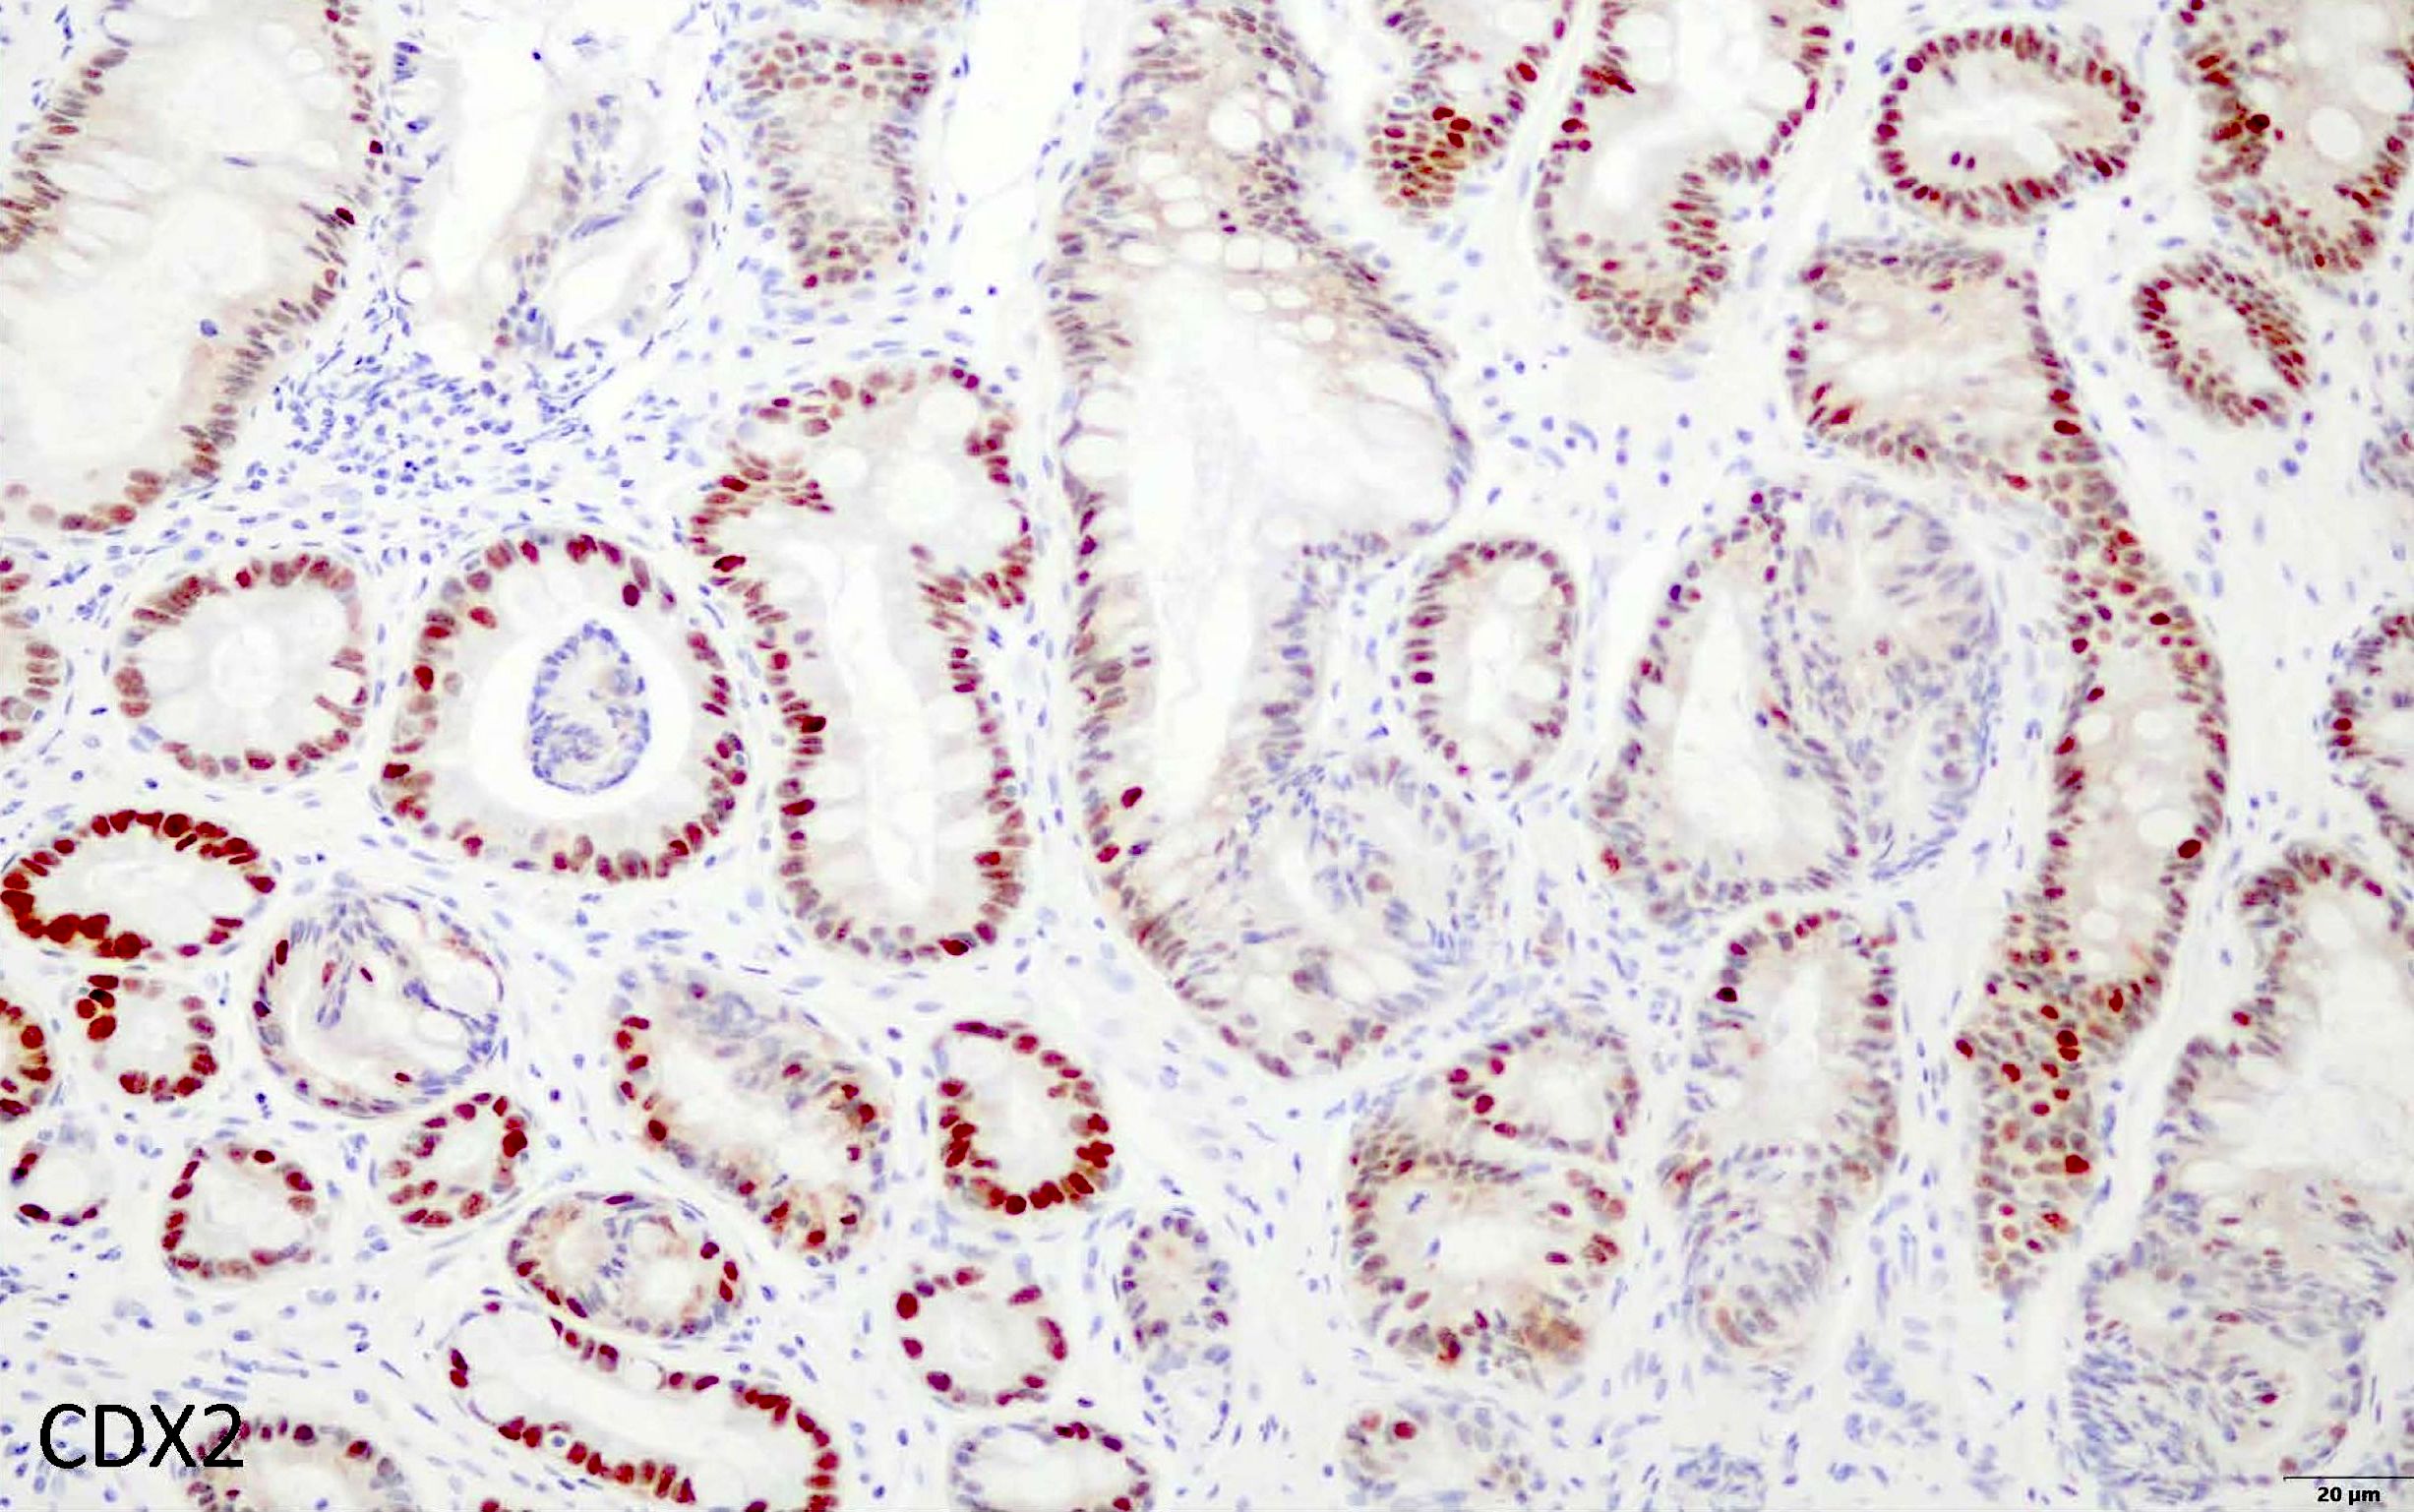

Positive stains

- CDX2: nuclear positivity of goblet cells and columnar mucosa (Gut Liver 2012;6:71)